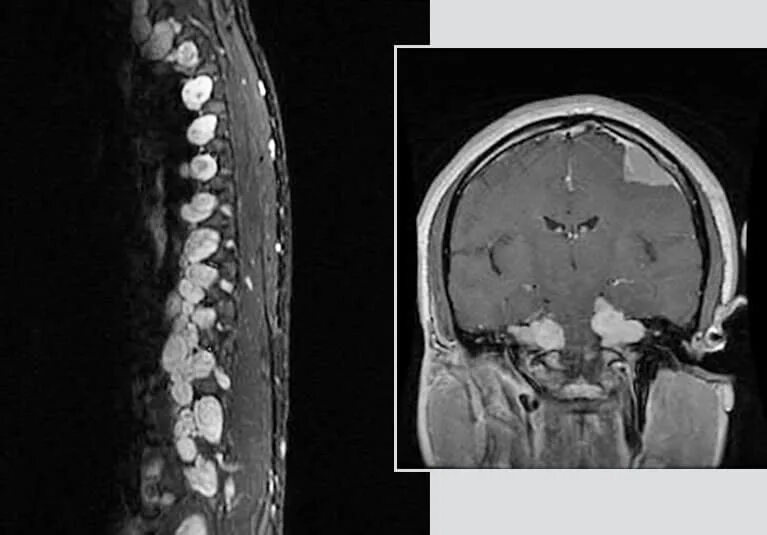

Нейрофиброматоз мрт